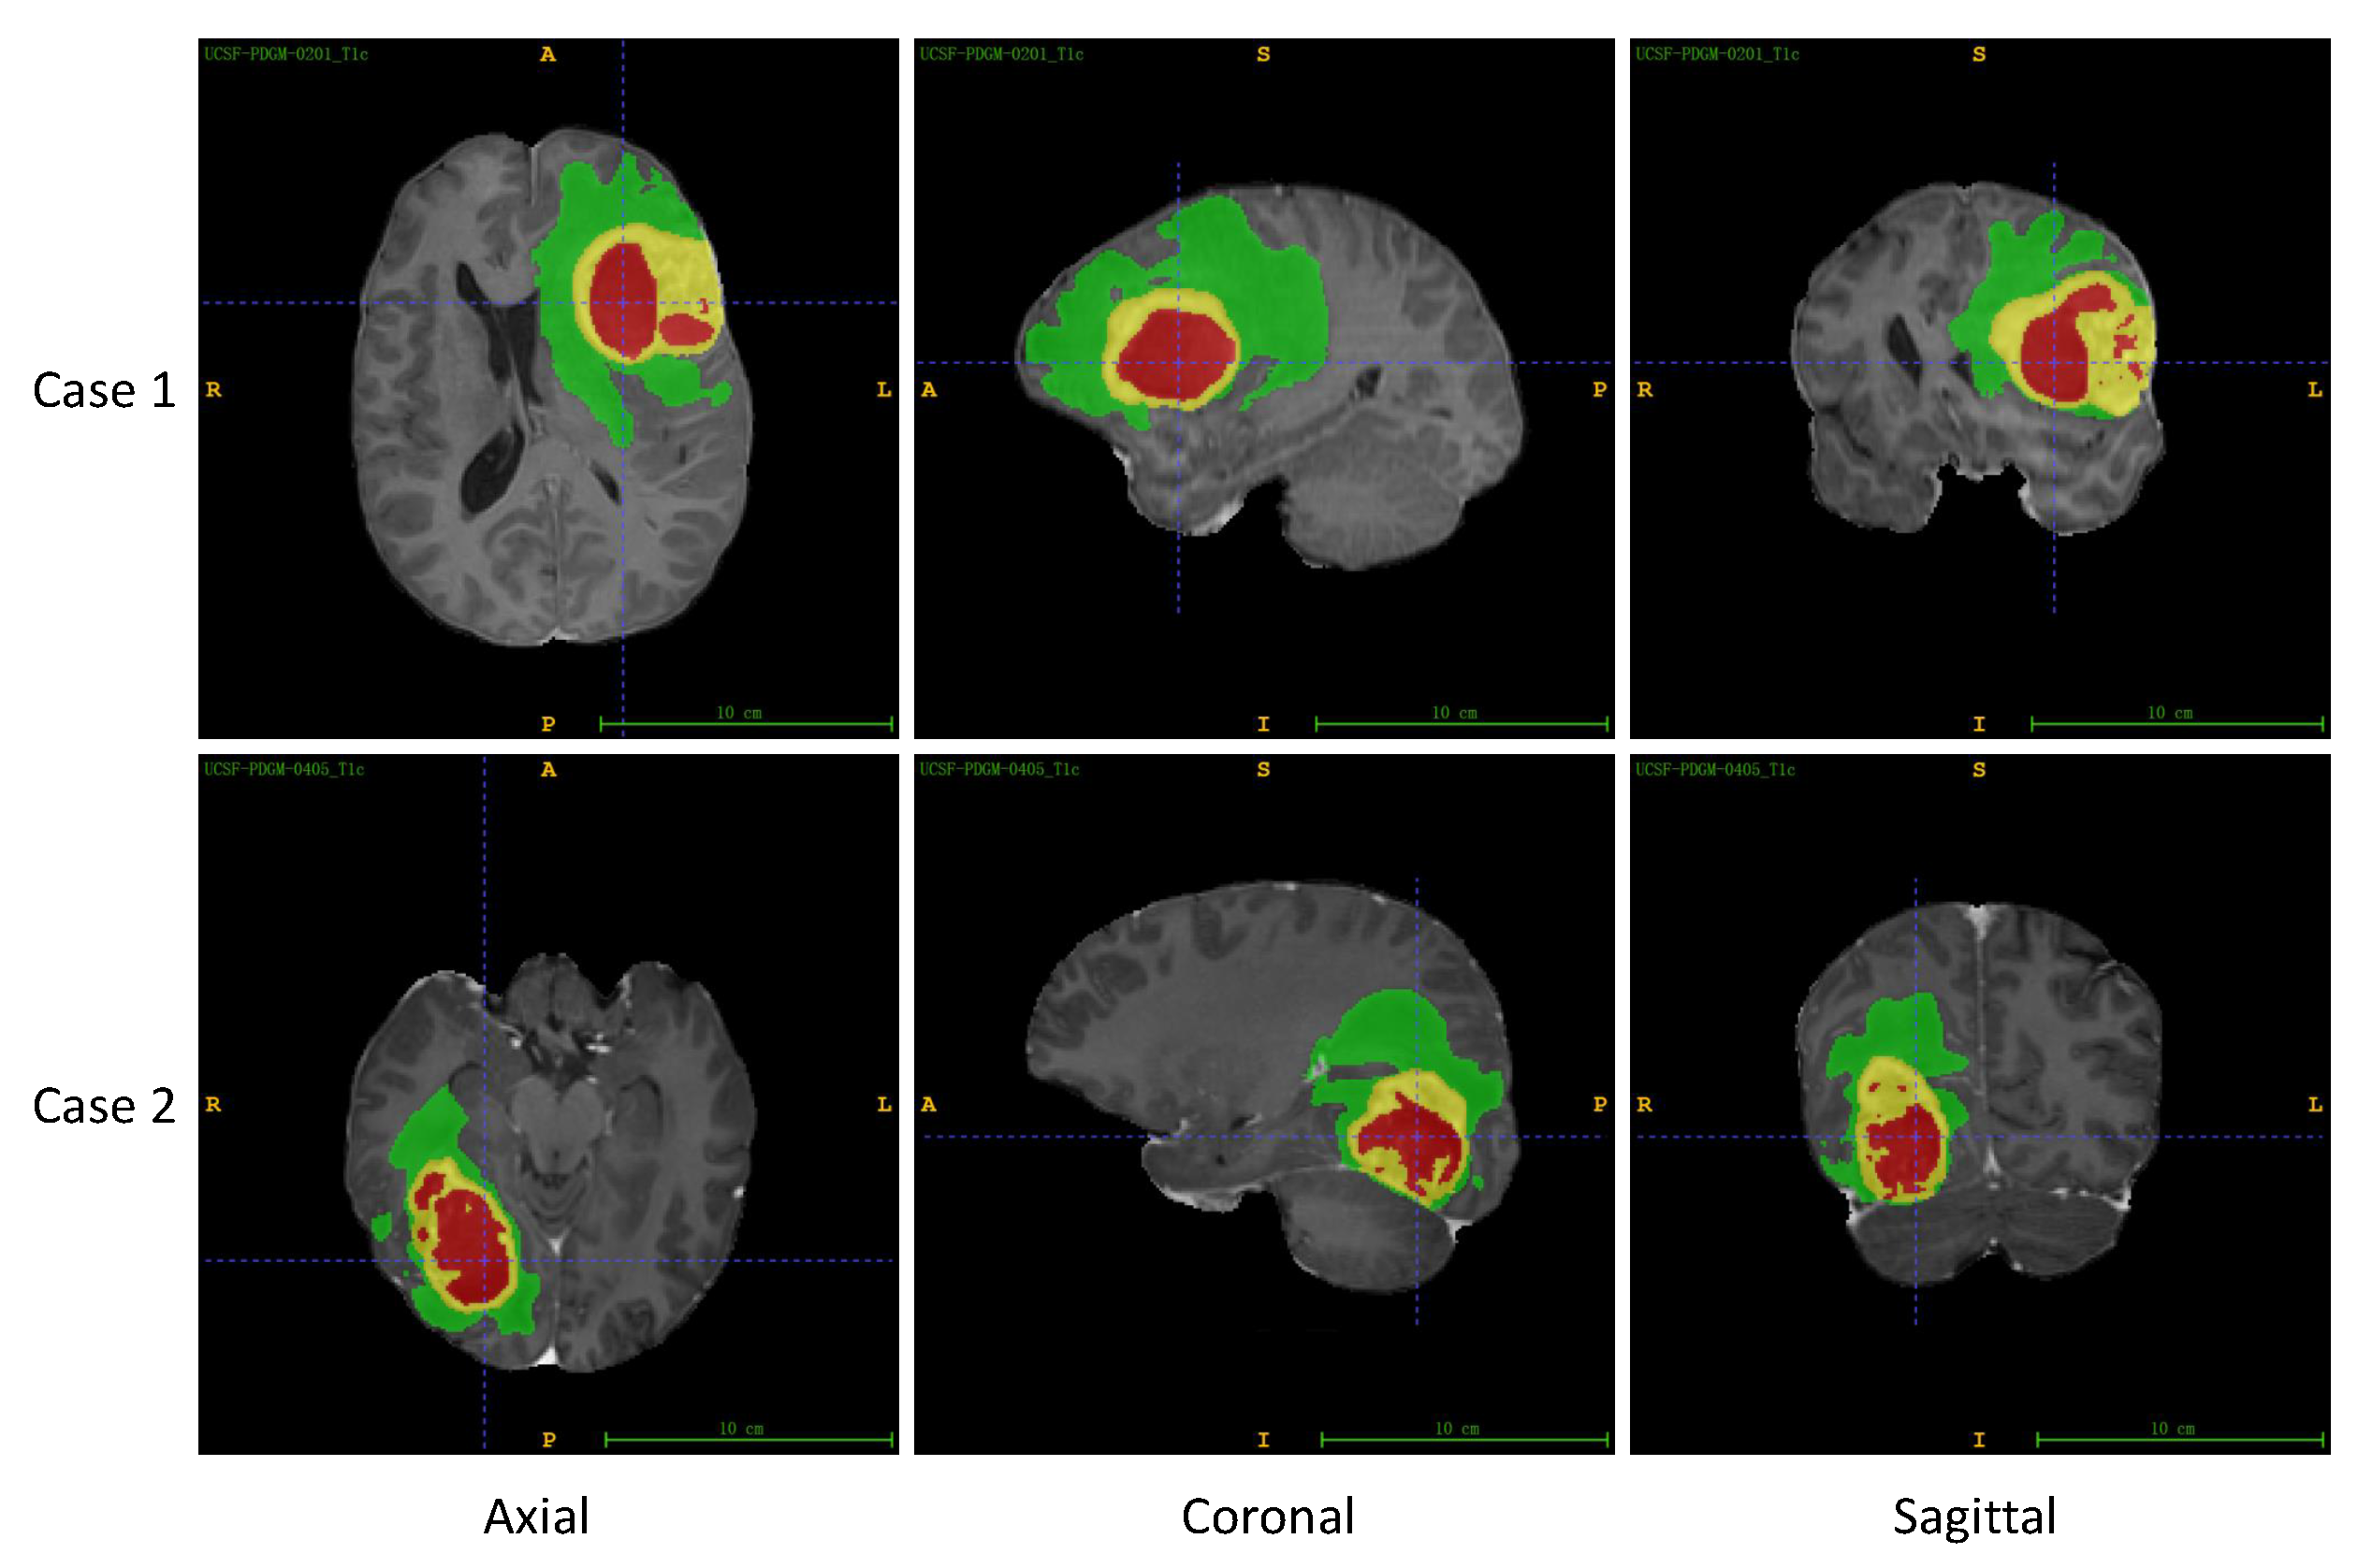

4.1. Datasets

- Calabrese, E.; Villanueva-Meyer, J.E.; Rudie, J.D.; Rauschecker, A.M.; Baid, U.; Bakas, S.; Cha, S.; Mongan, J.T.; Hess, C.P. The University of California San Francisco Preoperative Diffuse Glioma MRI Dataset. Radiol. Artif. Intell. 2022, 4, e220058. [Google Scholar] [CrossRef]